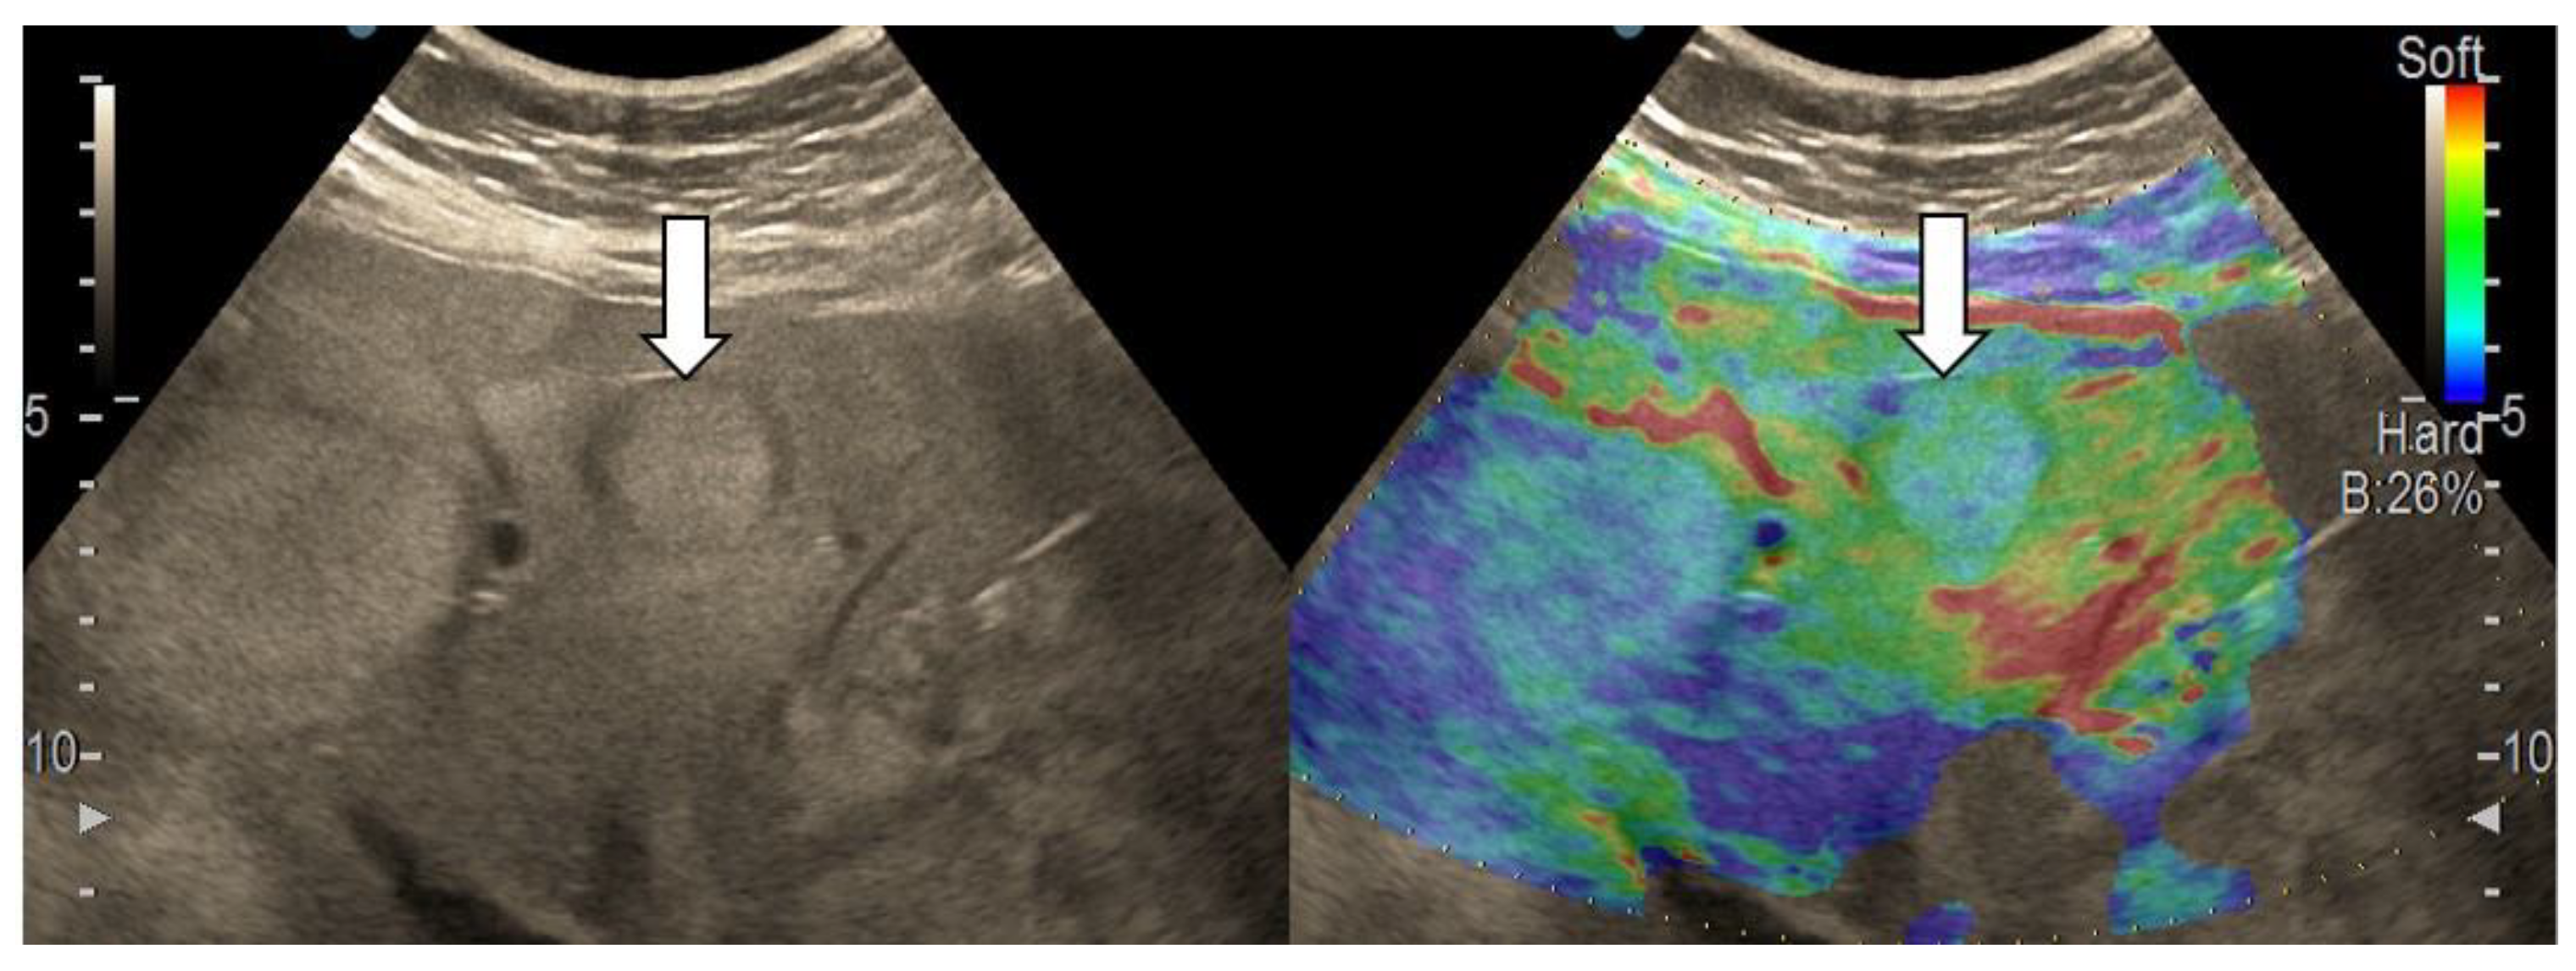

3.4. Real-Time Tissue Elastography

| Elasticity Type | Color Code |

|---|---|

| Type “a” | Homogenously green |

| Type “b” | Mosaic pattern with dominant green areas |

| Type “c” | Mosaic pattern with dominant blue areas |

| Type “d” | Homogenously light blue |

| Type “e” | Homogenously dark blue |

| RTE | Liver Adenoma | HMG | FNH | Complicated Liver Cyst | HCC | iCCA | Liver Metastases | Liver Lymphoma |

|---|---|---|---|---|---|---|---|---|

| Type “a” | 3 | 1 | ||||||

| Type “b” | 1 | 1 | 10 | 3 | 1 | |||

| Type “c” | 1 | 24 | 3 | 6 | ||||

| Type “d” | 1 | |||||||

| Type “e” | 5 | 3 | 1 |